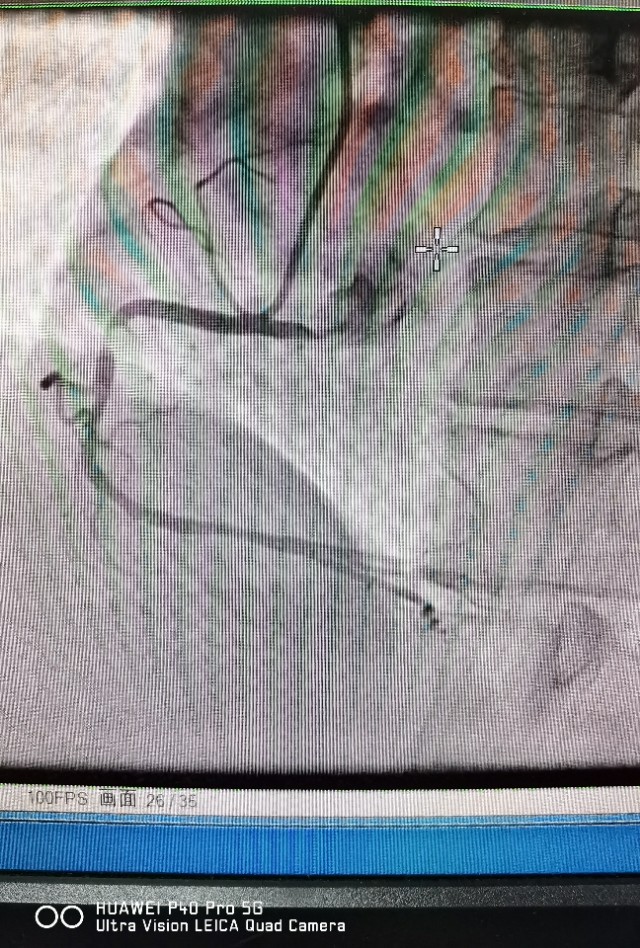

病例2 及时发现ACS斑块,避免心肌梗死发生

中年男性,反复不稳定心绞痛发作,冠脉CTA提示中重度病变,造影发现RCA弥漫病变,OCT发现冠脉内红色,白色血栓形成,随时可能发生心肌梗死!